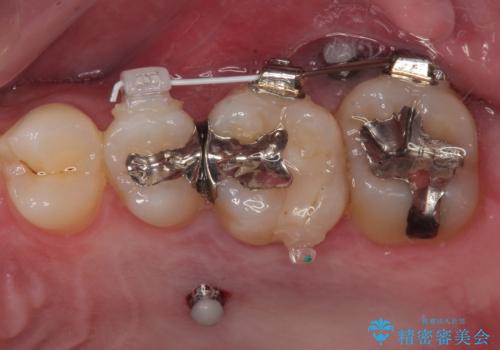

インプラント部は埋入とともに仮歯を装着し、同時に上顎奥歯の部分矯正を開始することとしました。

理想的な咬み合わせに改善した上で、インプラント補綴治療を行うこととしました。

部分矯正を行ったこと治療期間は長くなりましたが、違和感のない咬み合わせを達成することができました。